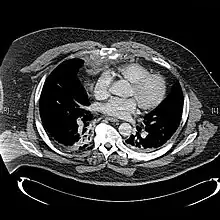

CT scan showing a comminuted sternal fracture.[12]

X-rays of the chest are taken in people with chest trauma and symptoms of sternal fractures, and these may be followed by CT scanning.[13] Since X-rays taken from the front may miss the injury, they are taken from the side as well.[14]